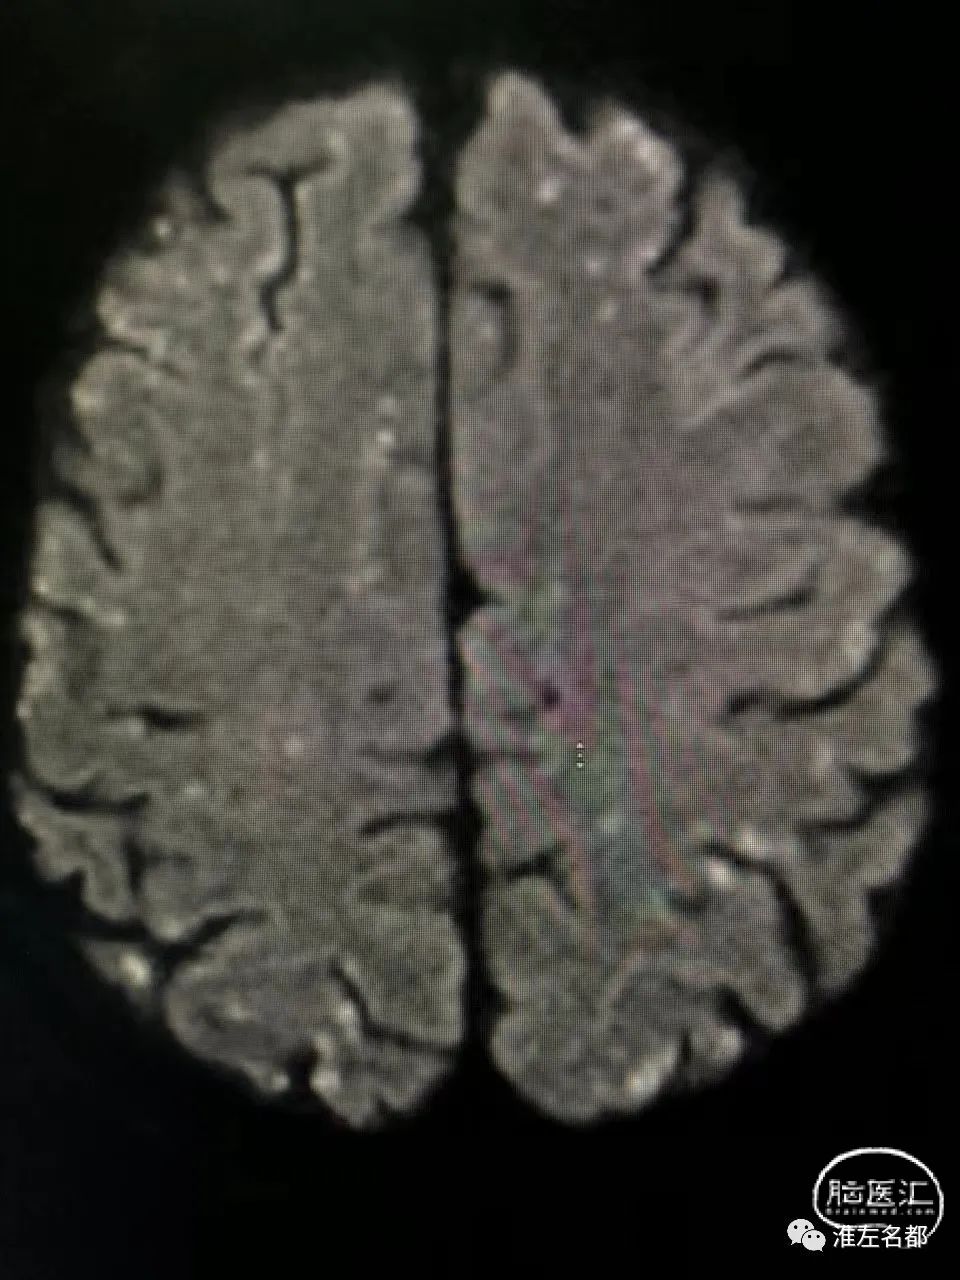

脑DWI:双侧半球皮质和皮质下弥漫分布的点状急性微小梗死灶。

第一,心源性栓塞梗死:患者心电图、心脏超声和心梗组合均提示心肌梗死,而心肌梗死是重要的心源性脑栓塞原因;该患者急性梗死病灶累及双侧半球多个脑动脉供血区,这个特征也是支持心源性栓塞的。

第二,还有一种可能的机制是,与肝癌栓塞治疗相关的反常栓塞:肝癌的肿瘤组织内是可能存在异常动-静脉瘘的,此时微小的球状介入栓塞材料就能通过这种瘘,经肝静脉进入下腔静脉和右心房,如果同时合并卵圆孔未闭,栓塞微球可经未闭的卵圆孔进入体循环,进而栓塞全身各个器官,包括脑和心脏。上述机制的支持点包括:患者53岁中年男性,而很大比率中-青年人群会合并卵圆孔未闭;患者术前无心脏疾病和心血管危险因素,术后即胸闷气促,这可能与介入用微球栓塞心肺的供血血管有关;由于微球直径很小,只会导致脑动脉远端的微小血管闭塞,所以脑梗死的范围很小,且弥漫分布。